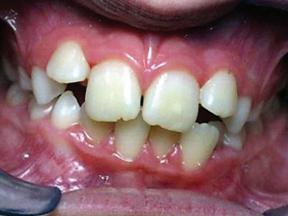

BEFORE AND AFTER PHOTOS

Empowering Dental Health with TeethXpress

TeethXpress implants have revolutionized dental care by offering a comprehensive solution for individuals struggling with missing or failing teeth. Let’s delve into the educational aspects of TeethXpress implants, focusing on their benefits and what to expect from this innovative procedure.

Immediate Results and Lasting Impact

One of the primary advantages of TeethXpress implants is the immediate results they offer. Unlike traditional dental implant procedures that may require multiple visits over an extended period, TeethXpress can often provide a complete set of new teeth in just a few hours. This quick turnaround time allows patients to swiftly regain their ability to eat, speak, and smile confidently.